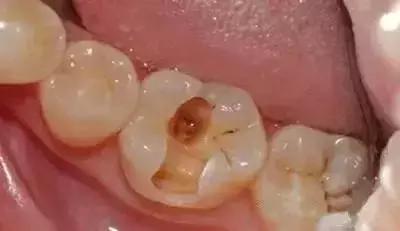

窝沟龋已经向两侧扩散,窝洞形成。这种情况下,窝沟可以明显用肉眼看出来,大块的,不规则的黑洞。在牙齿还没有疼之前,赶紧去牙科,去除黑色龋坏部分,再用补牙材料填充,及时止损,保护牙齿。